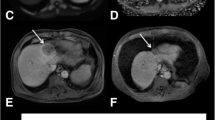

Figure 1 shows pretreatment quantitative MR images for a patient with tumor response and a patient without response to TACE, respectively. There were no significant differences in gender, involved lobe of the liver, ADC, and pre-TACE tumor size between response and nonresponse group (All p values ≥ 0.05). However, age > 60 (p value = 0.018) had a significant difference between two groups. D of tumor tissue in response group ([− 1.45 ± 4.87] × 10 − 3 mm2/s) was significantly higher than nonresponse group ([− 7.38 ± 4.96] × 10 − 3 mm2/s) (p value = 0.005). D* of tumor tissue in response group ([− 1.51 ± 4.83] × 10 − 3 mm2/s) was also significantly higher than nonresponse group ([− 7.41 ± 4.91 × 10 − 3 mm2/s]) (p value = 0.005). Meanwhile, f value of HCC tumor was significantly higher in response group ([0.51 ± 6]) than nonresponse group ([− 6.9 ± 5.89]) (p value = 0.004*) (Table 2).

Pretreatment MR images of two patients with responded and nonresponded lesions to TACE. a–d Pretreatment MR Images on the same slice of one lesion in segment eight and right lobe of the liver in a 40-year-old woman who did show tumor response to TACE. a–d IVIM-ADC, D, D*, and f maps, with the arrow showing the HCC lesion on the same slice with mean ADC, D, D*, and f values of 0.92 × 10 − 3 mm2/s, 1.04 × 10 − 3 mm2/s, 0.97 × 10 − 3 mm2/s, and 3.53 × 10 − 3 mm2/s, respectively. e–h Pretreatment MR Images on the same slice of one lesion in segment four and right lobe of the liver in a 40-year-old man who did not show tumor response to TACE. e–h IVIM-ADC, D, D*, f maps, with the arrowhead showing the HCC lesion on the same slice with mean ADC, D, D*, and f values of 0.9 × 10 − 3 mm2/s, 1.23 × 10 − 3 mm2/s, 1.4 × 10 − 3 mm2/s, and 3.9 × 10 − 3 mm2/s, respectively